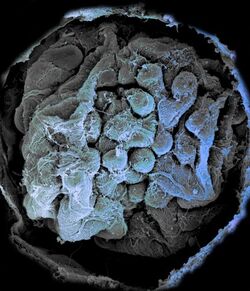

AG Moeller: We are investigating glomerular diseases in the kidney to develop novel therapeutic concepts. We also study how the kidney filter might work and why glomerular disease leads to proteinuria. A third focus are similar injury-induced transcriptional programs which play different roles in the glomerulus and the proximal tubule in acute kidney injury. For this we employ a broad spectrum of available methods such as transgenic animal models, isolated perfused kidneys, telemetric blood pressure measurements, high-end microscopy and single-cell transcriptomes.

AG Ostendorf/Floege: In the context of diagnosis and therapy of glomerular and tubulointerstitial kidney diseases, we focus on the research of central, pathophysiologically relevant mediators and their receptors in preclinical studies. In the recent past, we identified pro-fibrotic, pro-angiogenic, blood pressure-regulating and anti-proliferative molecules and systems that play a central role in the progression of kidney diseases and whose manipulation in preclinical medicine has shown new therapeutic potential. Using a broad spectrum of experimental models of renal inflammation and kidney damage, (conditional) transgenic animals, up-to date molecular and histological techniques, we currently focusing on studying a) the role of platelet-derived growth factor C (PDGF-C) and its receptor, b) the renal serotonin/serotonin receptor system in acute and progressive renal diseases and c) consequences of renal cell compartmentalization defects.